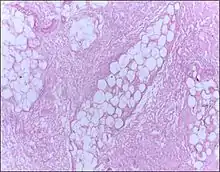

| Micrograph of breast tissue showing fat necrosis. H&E stain | |